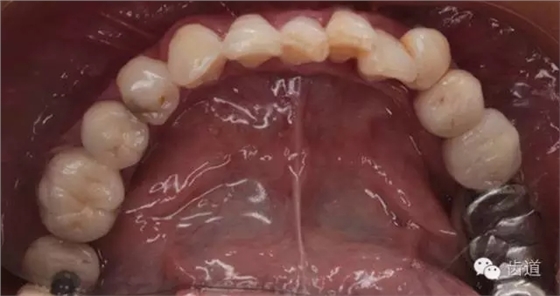

2、上頜牙合面觀